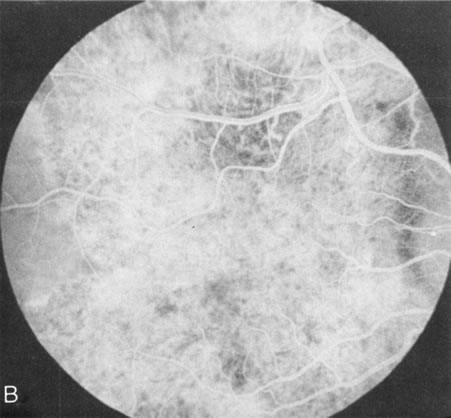

Fundus albipunctatus typically shows multiple, small white dots, which are deep in the retina, regular, and monotonous in their similar size, shape, and color and which involve the entire posterior pole into the equator while sparing the macula (Fig. 3A). These multiple dots are not apparent on FA. There may be a mottling of the background choroidal fluorescence and small areas of irregular transmission hyperfluorescence (especially surrounding the macula), but neither of these findings corresponds to the observed white dots8,9 (Fig. 3B).